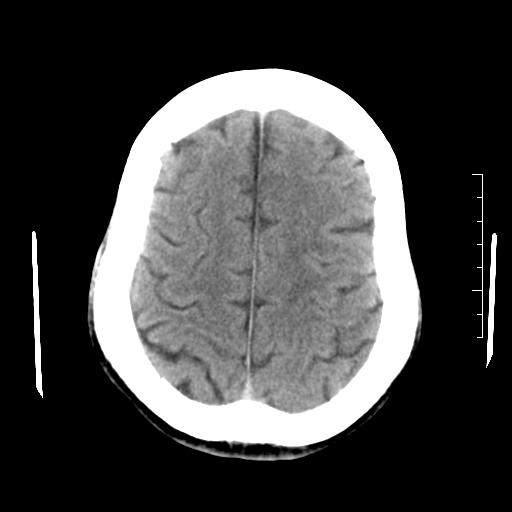

以下是引用随光逐影在2010-7-22 20:48:00的发言:[br]1)考虑左侧颞枕叶及左侧小脑脑梗塞。2)左侧半卵圆中心多发性腔隙性脑梗塞。[br]建议:必要时行mri检查。

以下是引用linyiming在2010-7-23 1:17:00的发言:[br])考虑左侧颞枕叶及左侧小脑脑梗塞。2)左侧半卵圆中心多发性腔隙性脑梗塞。[br]建议:必要时行mri检查。 [br]